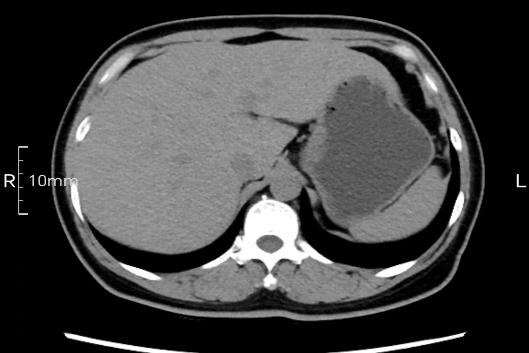

看看下面三幅便知遵醫(yī)囑的重要性。

完美禁食且喝飽飽,胃壁完美展現(xiàn)。

CT檢查前的“禁食”和“喝飽”,看似矛盾,實(shí)則合情合理,分工合作:空腹:是為了讓上腹部(肝膽胰脾腎等)的圖像清晰無(wú)干擾,并保障檢查安全。喝水:有效的充盈胃部和、腸道使圖像清晰呈現(xiàn)。兩者巧妙配合,都是為了給您一個(gè)最精準(zhǔn)的診斷結(jié)果。